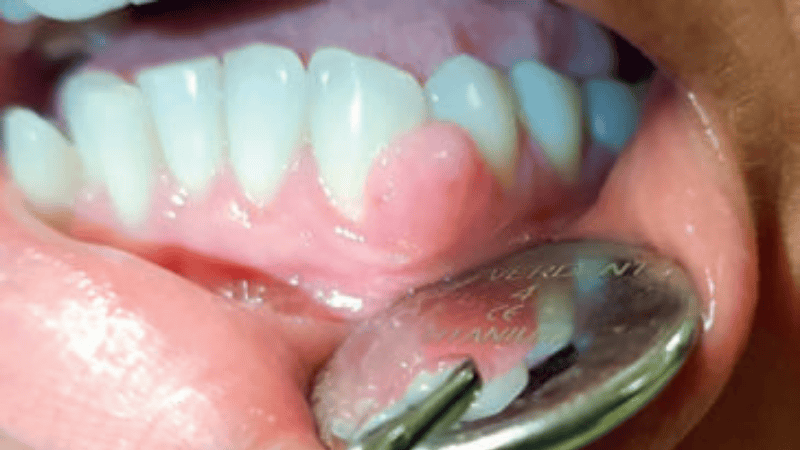

- Jakie są cechy charakterystyczne zapalenia dziąseł?

Streszczenie: Diagnostyka chorób dziąseł i przyzębia, które niestety nie są rzadkie, sprawia często trudności w warunkach gabinetu stomatologii ogólnej. Od kilku lat posiadamy nową klasyfikację chorób przyzębia i chorób tkanek wokół implantów, która w sposób gradacyjny, bardzo przejrzysty pozwala na ocenienie sytuacji pacjenta oraz zaplanowanie jego leczenia. Opierając się na najnowszej klasyfikacji chorób i zmian w obrębie tkanek przyzębia i tkanek wokół implantów z 2017 r., choroby dziąseł można podzielić na zapalenie dziąseł wywołane przez biofilm płytki nazębnej (ang. gingivitis) oraz choroby dziąseł niewywołane przez płytkę nazębną. Choroby dziąseł mogą być związanie z czynnikami ogólnoustrojowymi, jak i miejscowymi.